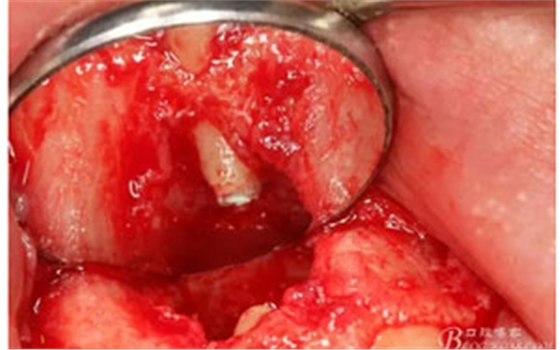

圖11。21囊壁被完整的剝離開來。

圖12.摘除的12根尖區(qū)的囊壁組織。

圖13.囊壁摘除后形成的骨腔,12牙根完全裸露在骨腔內(nèi)。